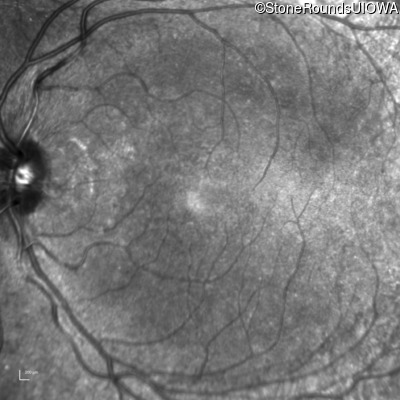

Infrared Fundus Photograph - Left - 20/20 -1

Exemplar